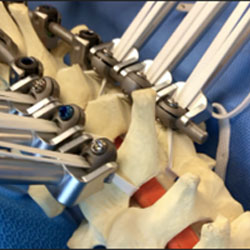

Early Failure of Locking Compression Plates in Pediatric Proximal Femoral Fracture